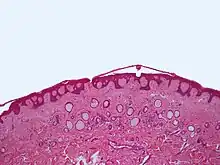

Syringomas can often be diagnosed clinically based on presentation, distribution patterns over the body, lack of associated symptoms, and family history. A definitive diagnosis requires a skin biopsy to allow the tissue to be examined under a microscope. Histologically, syringomas have a characteristic comma-shaped ("tadpole") tail of dilated, cystic eccrine ducts.